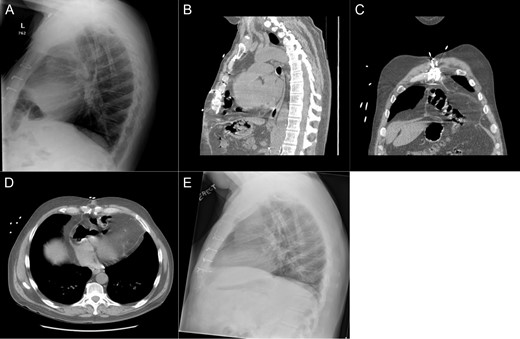

Imaging from Case #1. (A) Preoperative X-ray demonstrating loop of bowel in the thoracic cavity. (B) Preoperative CT scan, saggital view of diaphragmatic defect. (C) Preoperative CT scan, coronal view demonstrating colon passing through diaphragmatic defect. (D) Preoperative CT scan, axial view demonstrating intrapericardial transverse colon. (E) Postoperative X-ray demonstrating reduction of hernia contents.

Patient #1 is a 60-year-old male with a history of gastroesophageal reflux disease and ischemic cardiomyopathy. He underwent placement of a Heartmate II LVAD in 2013 before undergoing an orthotopic heart transplant (OHT) 2 months later. After an initially uncomplicated course, he presented to the emergency department 1 year following transplant with reflux, epigastric pain and a recent 10-pound weight loss. Prior endoscopic evaluations had been normal; however, a chest X-ray was suggestive of intrathoracic bowel. A subsequent CT scan demonstrated an intrapericardial hernia containing the transverse colon (Fig. 1A–D) and the patient was taken to the operating room for a robotic diaphragmatic hernia repair.

The patient’s postoperative course was uneventful. Postoperative imaging showed apparent resolution of the diaphragmatic defect (Fig. 1E). At 1 month, the patient was noted to be tolerating a regular diet without complaints of any dysphagia or reflux.